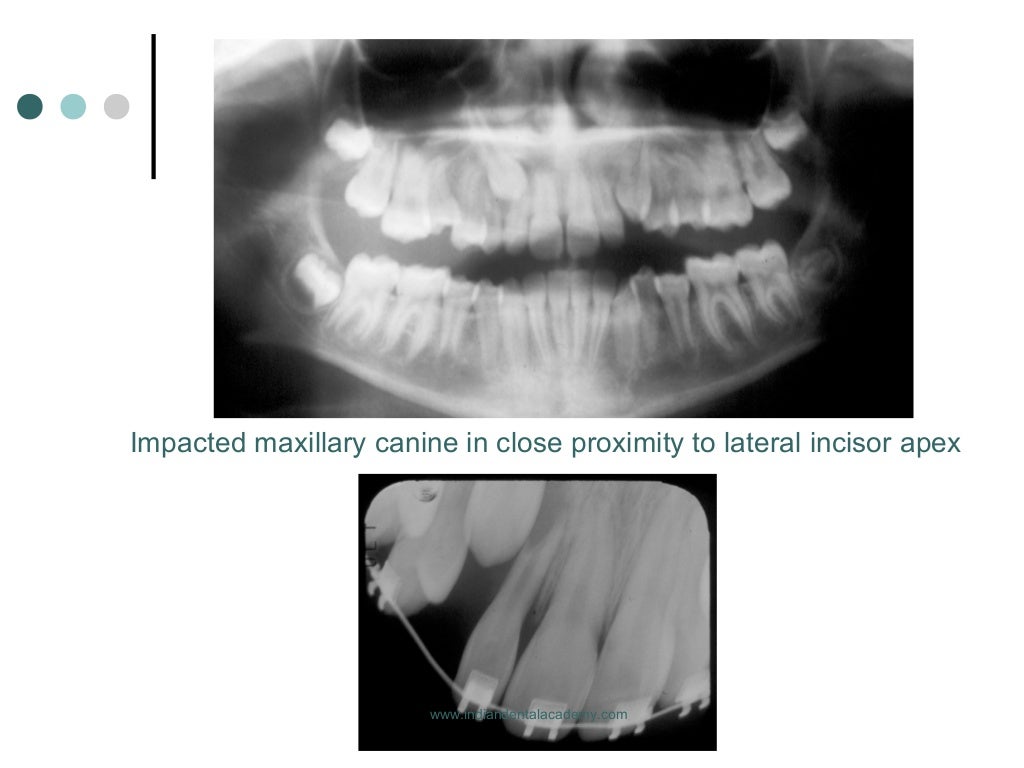

From www.slideshare.net

Root resorption in orthodontics /certified fixed orthodontic courses… Fixed Orthodontics Slideshare the document discusses the development and evolution of orthodontic appliances over time. steps for orthodontic emergencies: indications for the use of fixed appliances 1. appliance that are fixed or fitted onto the teeth by the operator and cannot be removed by patient is known as. We are prepared to handle the most common orthodontic emergencies. It. Fixed Orthodontics Slideshare.

Root resorption in orthodontics /certified fixed orthodontic courses… Fixed Orthodontics Slideshare Fixed appliances removable n tipping only n no control. indications for the use of fixed appliances 1. this document discusses fixed orthodontic appliances. the document discusses the development and evolution of orthodontic appliances over time. fixed orthodontic appliances dent 657. Correction of mild to moderate skeletal discrepancies as fixed appliances can be. Overbite reduction by intrusion. Fixed Orthodontics Slideshare.